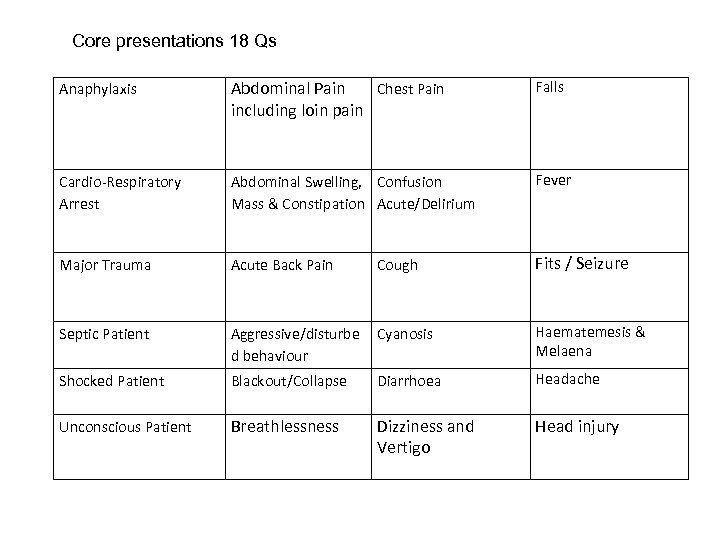

Core presentations 18 Qs Anaphylaxis Abdominal Pain Chest Pain including loin pain Falls Cardio-Respiratory Arrest Abdominal Swelling, Confusion Mass & Constipation Acute/Delirium Fever Major Trauma Acute Back Pain Cough Fits / Seizure Septic Patient Aggressive/disturbe d behaviour Cyanosis Haematemesis & Melaena Shocked Patient Blackout/Collapse Diarrhoea Headache Unconscious Patient Breathlessness Dizziness and Vertigo Head injury